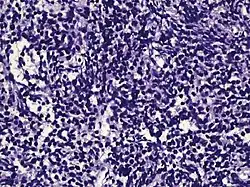

| Small-cell carcinoma | 0.3–2%[14][15][notes 1] | ![]() |

Half of cases have usual acinar components[1] |